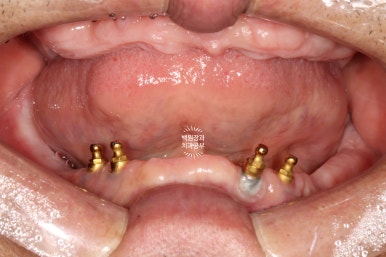

임플란트 2차수술을 하면 이렇게 임플란트 위치를 확인하실 수 있게 됩니다.

그리고 잘 유지된 각화치은의 양을 확인하실 수 있죠.

처음 내원하셨을 때 임플란트 주위염이 심했던 1개의 임플란트를 제외하고 3개의 임플란트는 이제 치아 머리를 얹어 새로운 쓰임을 기다리고 있는 중입니다.

임플란트를 몇 개 심고나니 뭔가 위치가 더 조화로워 보이지 않나요?